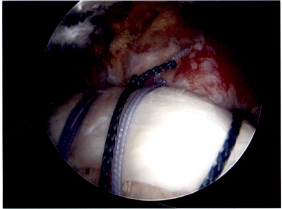

There are a number of different procedures based on the pathology. Generally, with partial thickness tears that have not responded to non-operative treatment the choice is arthroscopic surgery with debridement (shaving of the frayed tissue) of the rotator cuff often combined with removing bone spurs on the underside of the acromium. If there is significant arthritis in the ac joint that is symptomatic, a short section of the end of the clavicle may be removed at the same time. When a patient has a full thickness tear, the options are arthroscopic or mini-open rotator cuff repair. There is still debate about which procedure is more effective. In general, the quality of the open repair when tunnels are made in the bone (interosseous tunnels) has been felt to be stronger earlier in the healing process. Arthroscopic repair is dependent on inserting anchors in the bone to which sutures are attached. New arthroscopic devices and suture anchors, combined with a double row of anchors technique, have improved the quality of the repair. The only time an open repair is indicated is when bone tunnels are planned but if one is going to use anchors with an open incision, there is more trauma to the tissues than arthroscopic repair and overwhelmingly shoulder surgeons would not employ that technique. Post-operative sling immobilization and physical therapy rehabilitation is an integral part of the recovery to allow the tendon to heal to the bone. In the long run the repairs seem to have equivalent results with success of repair and range of motion. The advantage of the arthroscopic repair is the use of smaller incisions, decreased invasiveness (no muscles split) and the presumed decreased stiffness in the early postoperative phase. It is however important to note that some of rotator cuff repairs have some retearing of the tendon within one year of surgery, most without any symptoms because only a small portion of the repair retears. There is no correlation between the integrity of the repair and the resolution of patient symptoms. There are some rotator cuff tendons that cannot be repaired because the muscles have atrophied too much or the tendons have retracted or fibrosed and cannot physically be repaired. There is also the chronic situation where the lack of rotator cuff function has led to a severe type of arthritis called rotator cuff arthropathy which is amenable to a specific type of shoulder joint replacement.